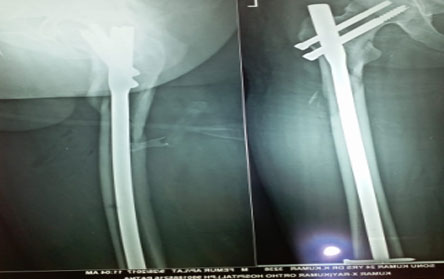

Trauma surgery:

Trauma surgery is a surgical specialty that utilizes both operative and non-operative management to treat traumatic injuries.

The Center of Orthopedics KUMAR ORTHO HOSPITAL ,Patna, offers the entire spectrum of modern orthopedic management, which is effective, patient - friendly & result oriented. In a nutshell, it is one stop treatment for all orthopedic ailments and fractures with emphasis on avoidance of complications, rapid mobilization, decreased period of confinement and an early return to normalcy.